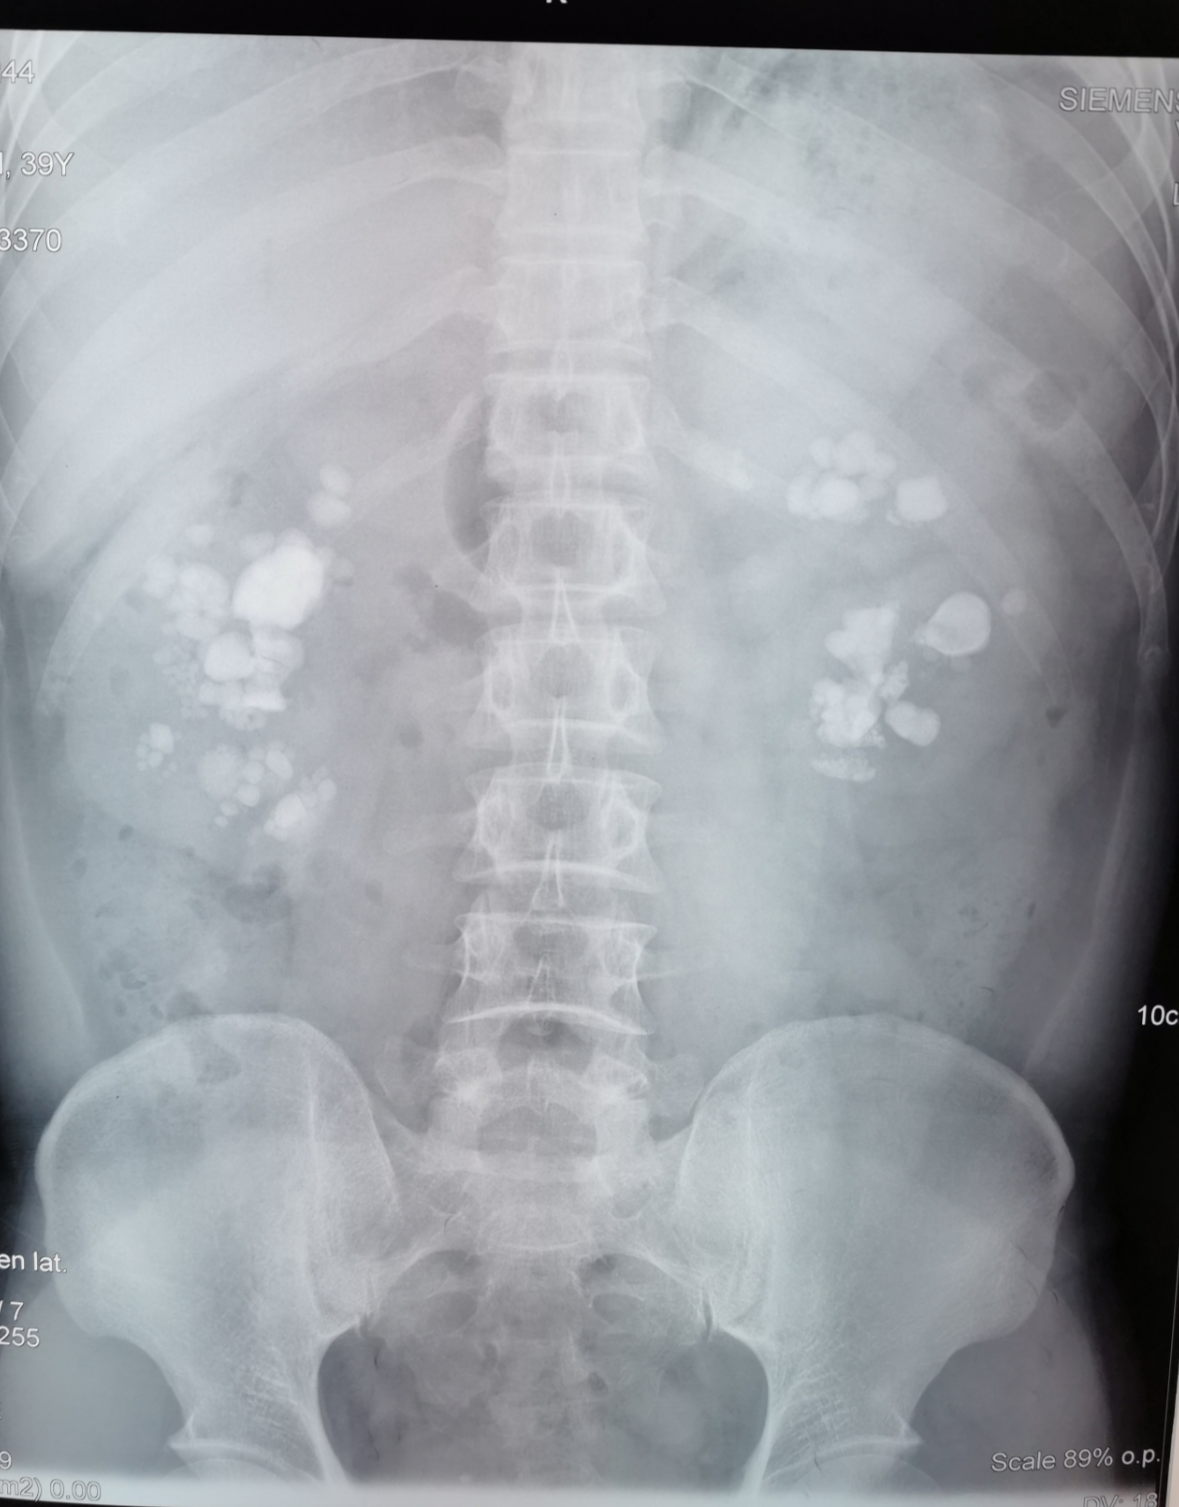

患者:罗先生; 年龄:40岁;15年来,双肾因巨大结石而导致双肾重度积水,双侧功能严重受损,甚至面临多发、复杂结石病变的威胁。

入住我院泌尿外科之后,在完善相关检查之后,泌尿外科团队确诊其为:双肾结石导致双肾重度积水,双侧功能严重受损,并面临多发、复杂结石病变的威胁。 因为患者病情重且较为复杂,双肾结石巨大,若进行手术,存在出血、感染加重的风险,且结石残留大。术中或术后出现大出血并无法止血,可能需栓塞肾动脉止血,导致肾功能不全(尿毒症),感染严重时也可引起尿源脓毒血症的发生导致患者死亡。但是如果不及时进行处理,肾里面巨大的结石长期刺激黏膜会引起慢性炎症或感染,严重者甚至会引发癌变。结石还可能引起尿路梗阻,尿路梗阻后可能导致输尿管和肾盂扩张、积水,损伤肾脏功能,严重时可造成肾功能不全(尿毒症),后期病情会越来越严重,直至肾功能完全丧失。 面对如此复杂的病情,泌尿外科团队反复进行讨论、仔细研判,一致认为:患者的治疗刻不容缓,因右肾结石较大、多发、复杂、感染,为保护左肾功能及避免脓毒血症,结石复杂且合并严重感染,不能一次性清除所有结石,并且手术时间不宜过长,需分期手术。

时间就是生命,罗先生的病情再也经不起一秒钟的耽搁。3月4号,就在患者入院两天后,在经过反复讨论和研判之后,泌尿外科副主任医师郭彤便带领团队,在手术麻醉科等团队的配合下,采用“双镜联合”的方法,为罗先生进行了经皮肾镜EMS碎石取石术。术后复查见右肾大部分结石已消失,残留结石有再次梗阻危害左肾功能风险,于是泌尿外科团队开始准备为患者进行第二次手术清理残石。 同样,第二次手术时泌尿外科团队采用了创伤小、恢复快的手术方式:经皮肾镜碎石取石术及左侧一次经皮肾镜碎石取石术,同时行在泌尿外科团队配合行左侧经皮肾镜碎石取石术+输尿管软镜双镜联合手术治疗。在泌尿外科和手术麻醉团队的努力下,经过两次手术,成功为罗先生清除了困扰他15年的结石。

经历两次手术后罗先生体内结石全部被清除